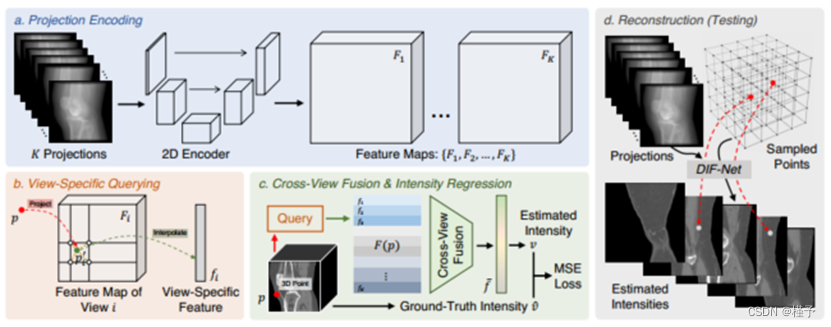

在此基础上,我们提出了一个新的重构框架,即DIF-Net DIF-Net首先从给定的K个二维投影中提取特征图,然后将给定的一个三维点按相应的成像参数投影到每个视点的二维成像板上,最后根据每个视点的二维成像板上的特征图,对每个视点的二维成像板上的点进行三维重建(距离、角度等)并从视图i的特征图中查询其视图特有特征。然后,来自不同视图的K个视图特定特征通过交叉通过引入连续强度场,可以用稀疏采样点集来训练DIF-Net以减少内存需求,与NeRF方法[5,14,19,21,29]相比,DIF-Net的设计具有相似的数据表示方法,可以在任意分辨率下重建CT体积(即隐式神经表示),但是可以引入额外的训练数据来帮助DIF-Net学习先验知识,DIFNet不仅可以在很短的时间内重建高分辨率CT,因为对于新的测试样本仅需要推理(无需重新训练),而且在视图极其有限的情况下,其性能也比基于NeRF的方法好得多。

2.1 强度场

我们将CT体积公式化为连续强度场,其中该场中的3D点p ∈ R 3的属性表示其强度值v ∈ R。强度场可以定义为连续函数g:R3 → R,使得v = g(p)。因此,重建问题可以重新表述为从K个投影I = {I1,I2,.. .,IK},即v = g(I,p)。基于上述公式,我们提出一种新的重建框架,即DIF-Net,用于执行有效的稀疏视图CBCT重建,如图2所示。

2.2 DIF-Net:深度强度场网络

DIF-Net首先使用共享的2D编码器从投影I中提取特征图{F1,F2,.,FK}<$R C×H×W,其中C是特征通道的数量,H/W是高度/宽度。在实践中,我们选择U-Net [18]作为2D编码器,因为它具有良好的特征提取能力和在医学图像分析中的流行应用[17]。然后,给定一个3D点,DIF-Net收集从不同视图的特征图中查询的视图特定特征,以进行强度回归。

视图特定特征查询。考虑3D空间中的点p ∈ R 3,对于具有扫描角度αi和其他成像参数β的投影视图i,(距离、间距等),我们将p投影到视图i的2D成像面板上,并获得其2D投影坐标p ′ i = φ(p,αi,β)∈ R 2,其中φ(·)是投影函数。投影坐标p ′ i用于从视图i的2D特征图Fi查询视图特定特征fi ∈ R C:

跨视图特征融合和强度回归。给定K个投影视图,从不同视图查询点p的K个视图特定特征以形成特征列表F(p)= {f1,f2,.,fK}<$RC。然后,引入交叉视图特征融合δ(·)从F(p)中收集特征并生成一维向量<$f = δ(F(p))∈ R C来表示p的语义特征。一般来说,F(p)是一个无序的特征集,这意味着δ(·)应该是一个集合函数,可以用池化层来实现在我们的实验中,训练样本和测试样本的投影角度是相同的,从0 μ m到180 μ m均匀采样因此,F(p)可以看作是一个有序列表(K×C张量),和δ(·)可以由2层MLP实现(K → → 1)进行特征聚合。我们将在消融研究中比较δ(·)的不同实现。最后,对f应用4层MLP(C → 2C → <$C2 <$→ <$C8 <$→ 1)以回归强度值v ∈ R。